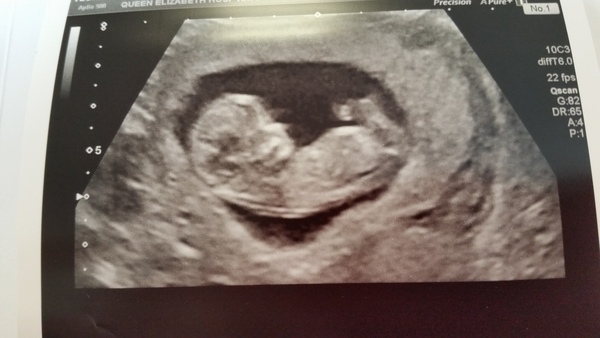

I had a small bout of pinky red spotting Wednesday night and yesterday. Due to my history I was told to phone epu. Had nothing but browny yellow since yesterday afternoon, went in for scan this morning and lovely little baby gave us a wave Grin Been put back 2 days again to 9+3 but sonographer said very common at this stage, also spotting common but they wanted to check.

So here's Choccy not-so-much-a-bean-but-a-proper-little-person!!